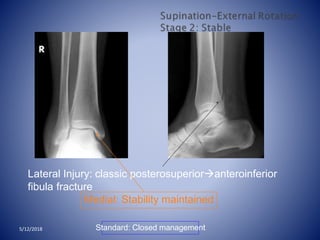

Stage 1 Anterior

tibio- fibular

ligament

Stage 2 Fibula fx

Stage 3 Posterior

malleolus fx or

posterior tibio-

fibular ligament

Stage 4 Deltoid

ligament tear or

medial malleolus

fx5/12/2018

Lateral Injury: classic posterosuperioranteroinferior

fibula fracture

Medial: Stability maintained

Standard: Closed management5/12/2018